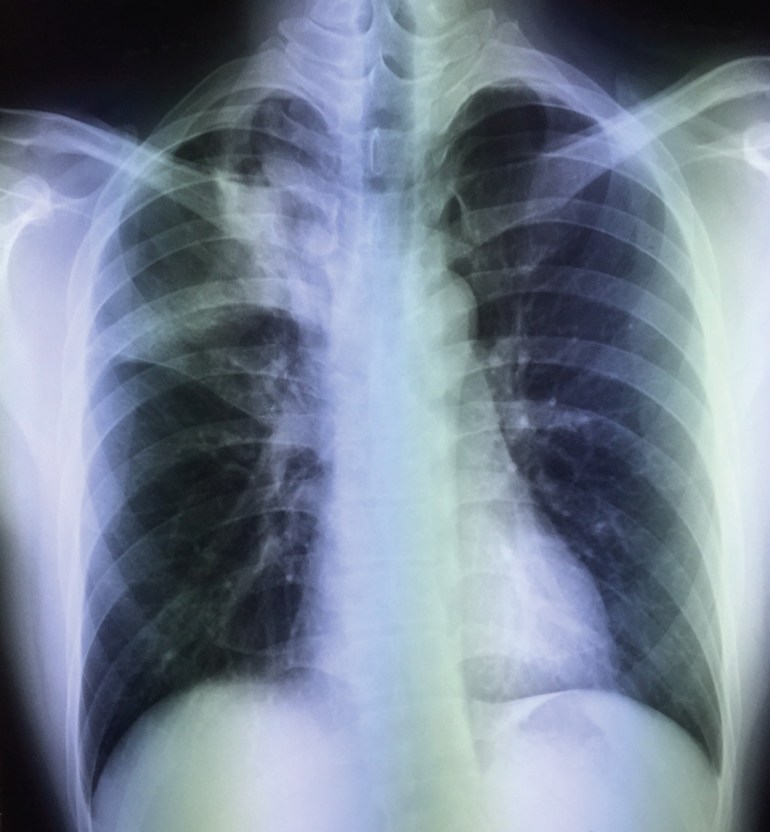

He had started to develop a dry cough a week later, although he did not have any fever or other constitutional symptoms. A repeat chest X-ray showed progression of radiological changes.

The most likely diagnosis remains pulmonary tuberculosis despite the negative sputum smears and TB PCR, because of the radiological appearance, the lack of any major immunosuppressive condition, and the relatively high rates of tuberculosis locally. He is also not in the age group where cancer is likely. The conundrum is whether to further investigate or start therapy. “Watchful waiting” is not a good option as there has been obvious radiological progression. The issue with further investigation is that a more invasive procedure, such as bronchoscopy with bronchoalveolar lavage and possibly transbronchial lung biopsy, will be necessary, with its attendant risks. A CT thorax is unlikely to yield more information that will impact on a therapeutic decision. The issue with empirical TB therapy is, naturally, what if this is not TB?

In any case, the pros and cons of each choice was discussed with the patient and empirical TB therapy was initiated. He tolerated the drugs well, cough resolved after a week, and follow-up chest X-rays showed progressive improvement as well. A significant minority of pulmonary TB cases in Singapore are culture negative.